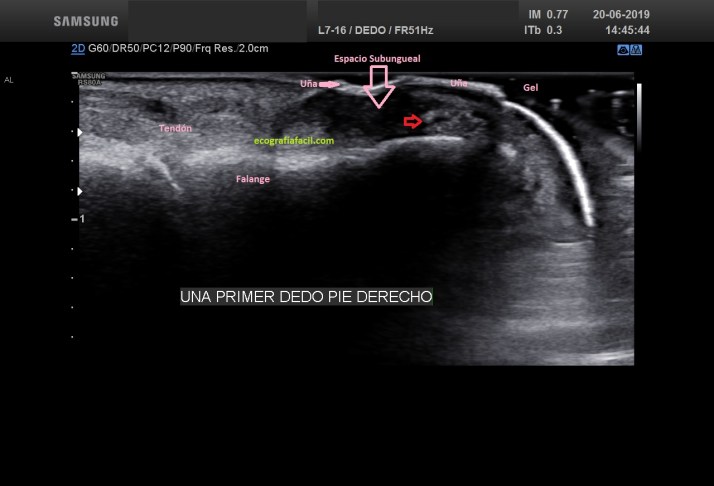

La exploración es la que tienes enlazada en el primer párrafo. Mucho gel, nada de presión con la sonda y localización de la uña (hiperecogénica zona superficial y ligeramente curva), después el espacio subungueal, hipoecogénico que da comienzo afiládamente en la raíz. Es vital tener claro otros tejidos, como los tendones extensores y el hueso.Mira:

The exploration is the one you have linked in the first paragraph. A lot of gel, no pressure with the probe and location of the nail (hyperechogenic surface area and slightly curved), then the subungual, hypoechogenic space that begins sharply at the root. It is vital to be clear about other tissues, such as extensor tendons and bone.

Observa la ecoestructura, sobre todo para a observar el espacio subungueal (bajo la uña), homogéneo, hipoecogénico…»limpio». Ahora quiero que te fijes muy bien en la siguiente imagen. Es la patológica, compara:

Observe the eco-structure, especially to observe the subungual space (under the nail), homogeneous, hypoechogenic … «clean.» Now I want you to look closely at the following image. It is the pathological, compare: